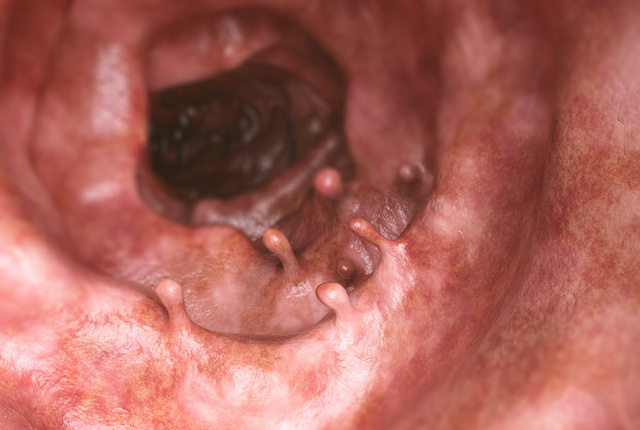

大腸の管の内側表面は粘膜でできており、この粘膜の最も浅い層の一部がイボのように隆起してできたものを大腸ポリープといいます。多くは隆起しますが、平坦なものやキノコのように茎を持ったものなど形状は様々です。構造や組織により、腫瘍性ポリープと非腫瘍性ポリープに分けられ、専門的にはさらに細かく分類されています。腫瘍性ポリープは、良性の大腸腺腫と悪性の大腸がんがあり、非腫瘍性ポリープは、過形成性ポリープ、炎症性ポリープ、過誤腫性ポリープに分類されます。非腫瘍性ポリープは加齢や炎症によるもので、大きいものを除いては特に治療を必要としませんが、腫瘍性ポリープは良性であっても大腸がんになる可能性があるため注意が必要です。

内視鏡治療の適応となるポリープは、一般的には「径6ミリ以上の良性のポリープ」と「リンパ節転移の可能性がほとんどなく内視鏡を用いて一括で切除できるがん」です。ただし、径5ミリ以下の良性ポリープでも、平坦あるいはへこんだ形のもの、がんとの区別が難しいものは適応となります。